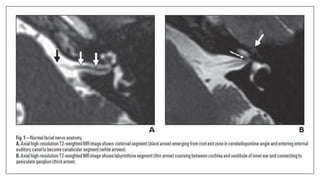

• Ho ML, JulianoA, Eisenberg RL, MoonisG. Anatomy and pathology of facial nerve. AJR. 2015; 204:W612–

W619